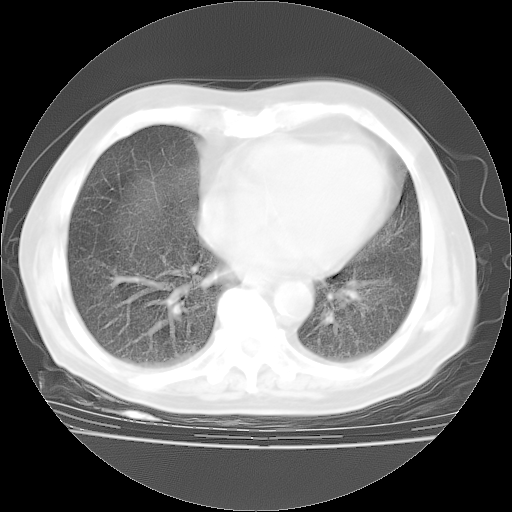

4月28日肺部CT——再次出现类似去年5月9日——透光度降低,“间质性”改变。

4月28日肺部CT——再次出现类似去年5月9日——磨玻璃样、间有“粟粒样”改变。

个人阅读4.14日肺部CT平扫:纵隔窗无异常,但肺窗示:双下肺内、后基底段有片絮状侵润影,部位以后基底段为著,以间质改变为主,呈急性肺泡炎征像,和首次住院影像学有相似之处。仅是个人读片,明日请相关专家再读片哈。其它建议同上。